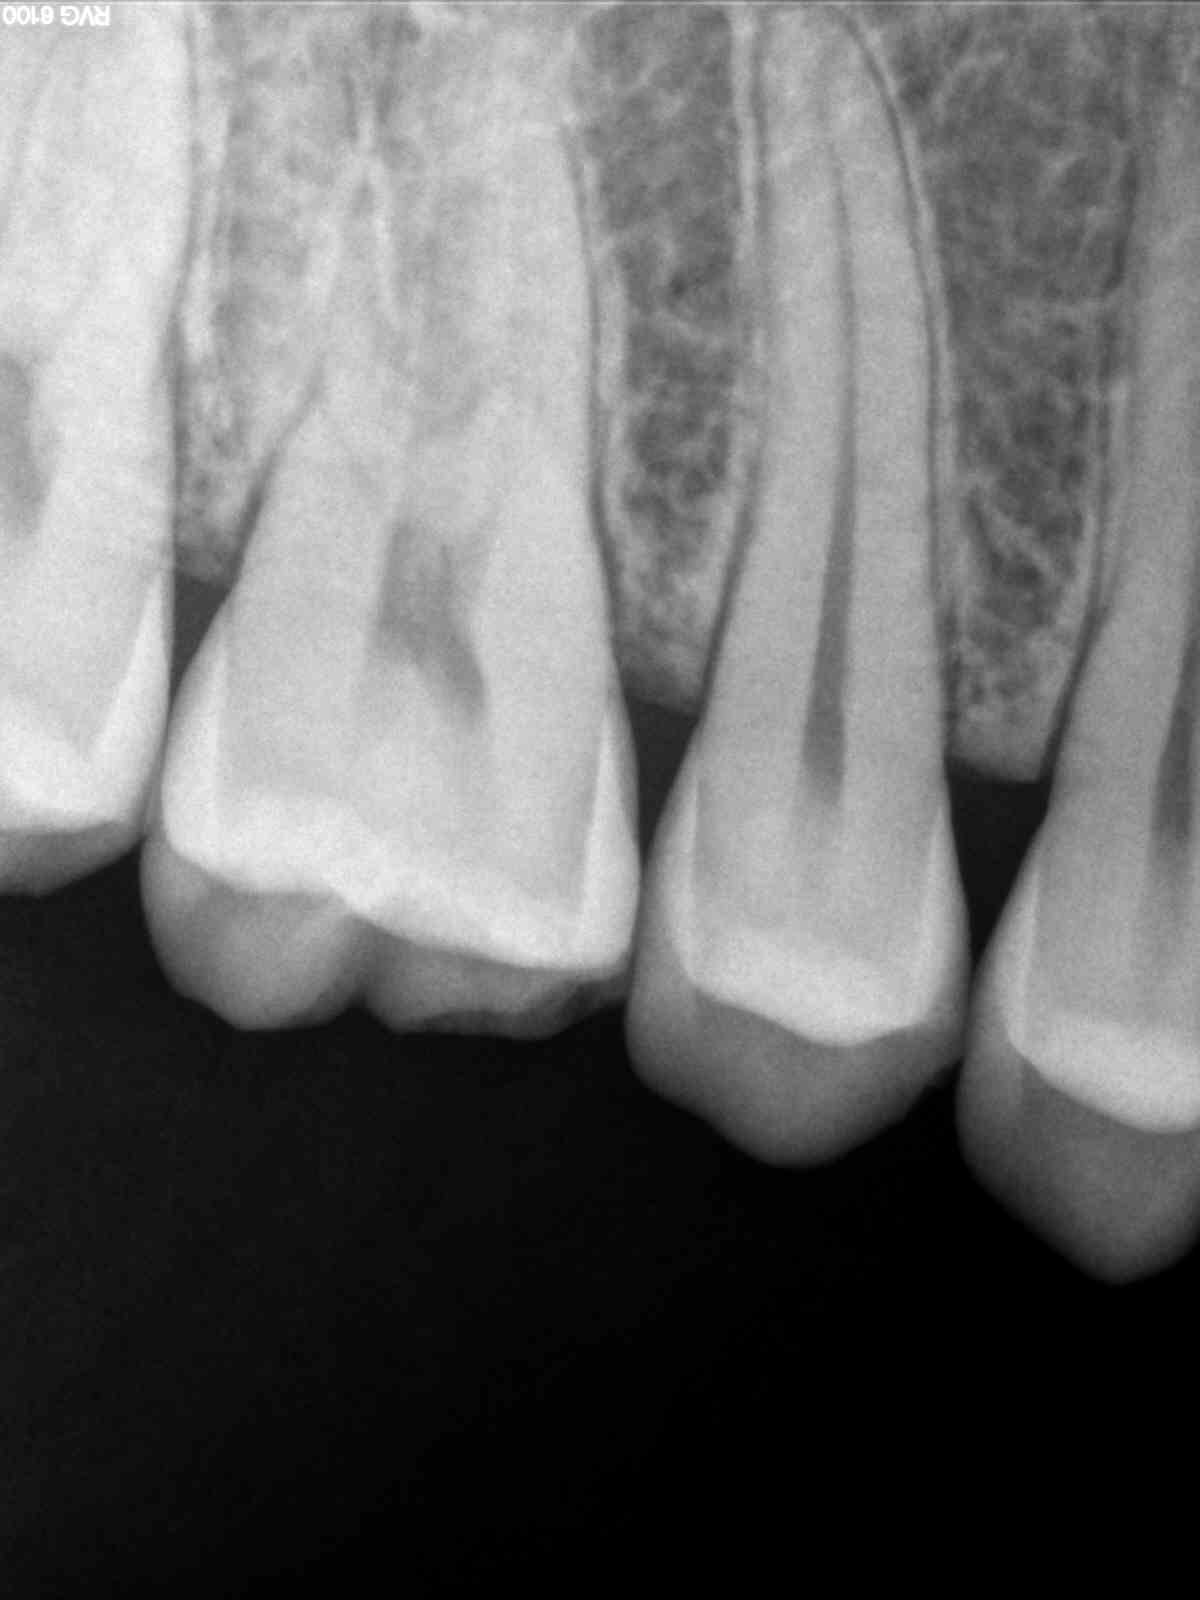

Par ex endo 26

Deux radios : la première avec l'ancien capteur trophy

et la seconde avec le nouveau 6100.

Carie 15/16 avec le nouveau capteur Kodak 6100 ... On voit quasi rien sur la préop

et après les compos, carie curetée ... il y avait bien quelque chose ... :(

Enfin, je ne verrai plus les "petites" lésions avec ce capteur, ce qui n'est pas un mal ?! ^^